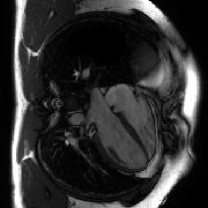

The proposed method is tested on the retrospective cardiac cine dataset OCMR[53]. The detailed information of the dataset is listed in the supplementary file. The acquired data are transformed into the -space domain using the multi-channel NUFFT implementation with golden-angle radial trajectories based on Fibonacci number sequencing. Coil sensitivity maps are derived through the ESPRIT algorithm[54] to enable parallel imaging reconstruction. Different acceleration factors (AFs) are simulated for evaluation, including 21, 13, 8, 5, 3, 2, 1 spokes per frame (AF=9.7, 15.7, 25.5, 40.8, 67.9, 101.9, 203.7).

| NUFFT | GRASP | FMLP | InstantNGP | GridTD | Original |

We select four representative baselines, including the NUFFT that provides direct zero-filled reconstructions without additional processing; the GRASP [39] that incorporates temporal frame grouping, time-averaged coil sensitivity estimation, and TV regularization; the FMLP [41] that employs INR and Fourier feature encoding for reconstruction; and the InstantNGP [24] that employs the multi-resolution hash grid encoding for dynamic MRI reconstruction.

IV-C2 Results

The quantitative results for compressive dynamic MRI reconstruction are shown in Table V. The proposed GridTD method outperforms competing methods across all evaluated settings in PSNR and SSIM metrics. Compared to other unsupervised deep learning methods FMLP and InstantNGP, our GridTD is over 50% faster due to the compact model structure. In Fig. 6, we present some visualizations of the reconstructed MRIs and the corresponding error maps, which demonstrate that GridTD better preserves structural edges and robustly recovers fine details, showing the superiority of our method for dynamic MRI reconstruction. All these results on video SCI, spectral SCI, and dynamic MRI reconstruction validate the strong performance of GridTD, positioning it as a versatile and state-of-the-art approach for compressive imaging reconstruction.